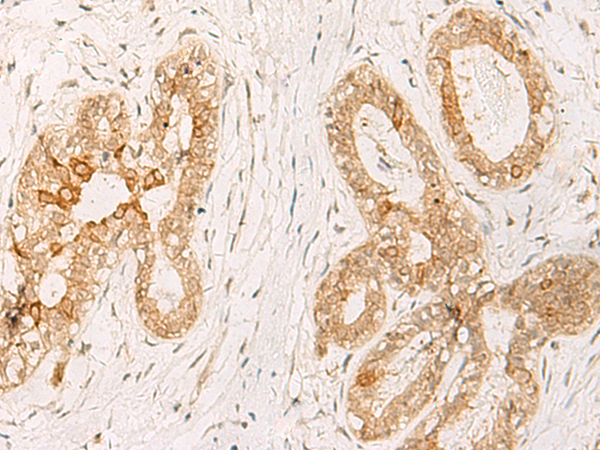

分类: 科研抗体货号: P13585别名: FBRNP; HNRPA3; D10S102; 2610510D13Rik应用: WB,IHC反应种属: Human, Mouse, Rat